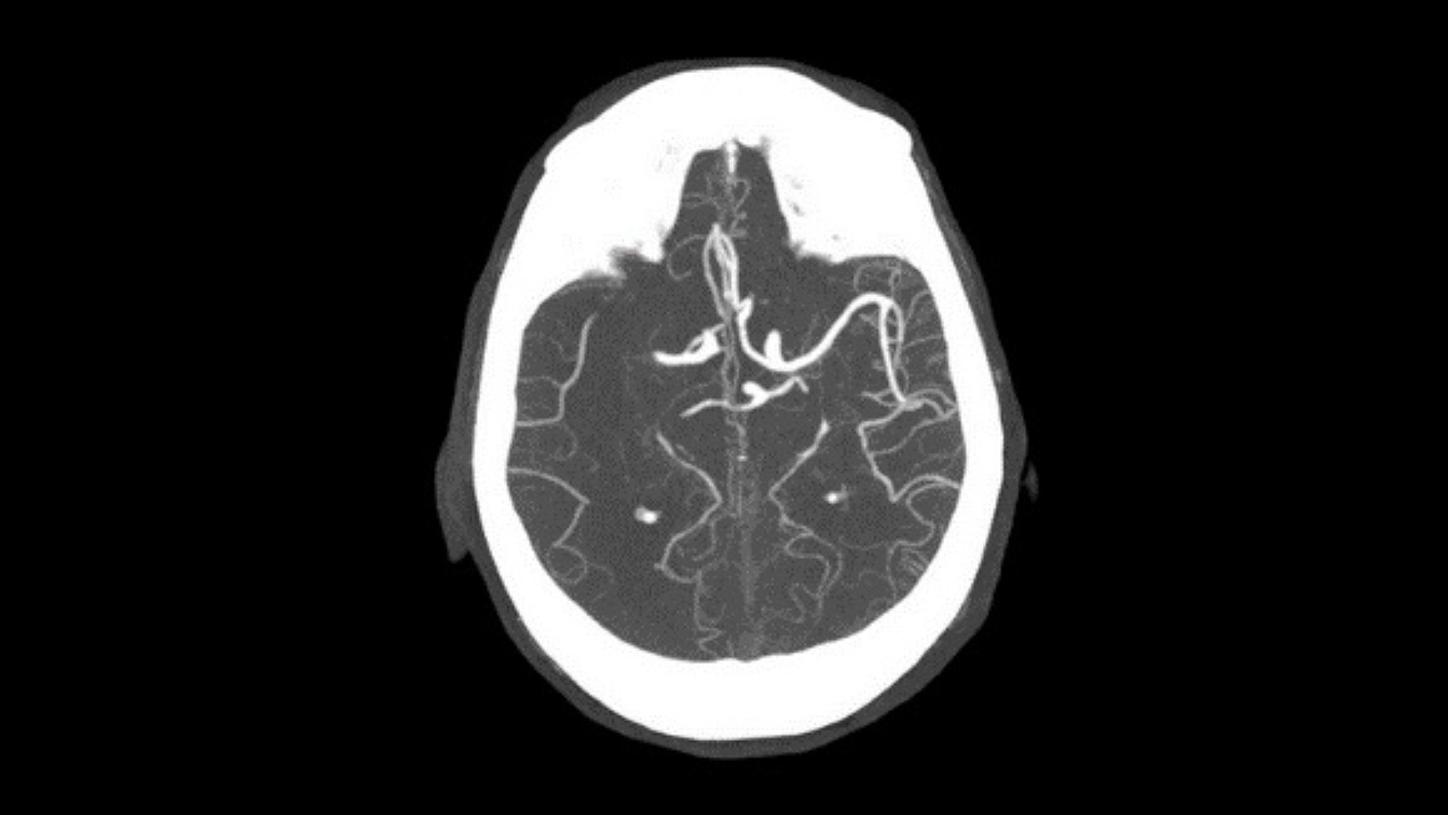

Angiography

CT planning of the following treatment with definition of occlusion length and collateral status and automated bone removal